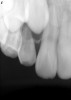

Figure 5  Retreatment of the case shown in Figure 4.

Figure 5